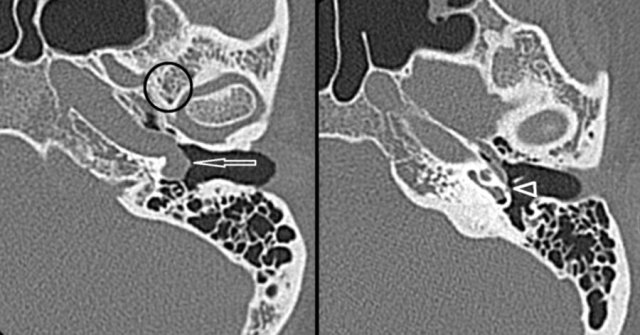

Aberrant course of ICA or stapedial artery

An aberrant course of the internal carotid artery and persistence of the stapedial artery are congenital variants that need to be recognized on imaging studies.

An aberrant course of the internal carotid artery in the middle ear may mimic a soft tissue mass or paraganglioma at otoscopy.

On the left an Aberrant course of the internal carotid artery (arrow) and persistence of the stapedial artery (arrowhead) on thin-sliced CT.

Note the absence of the foramen spinosum (encircled).